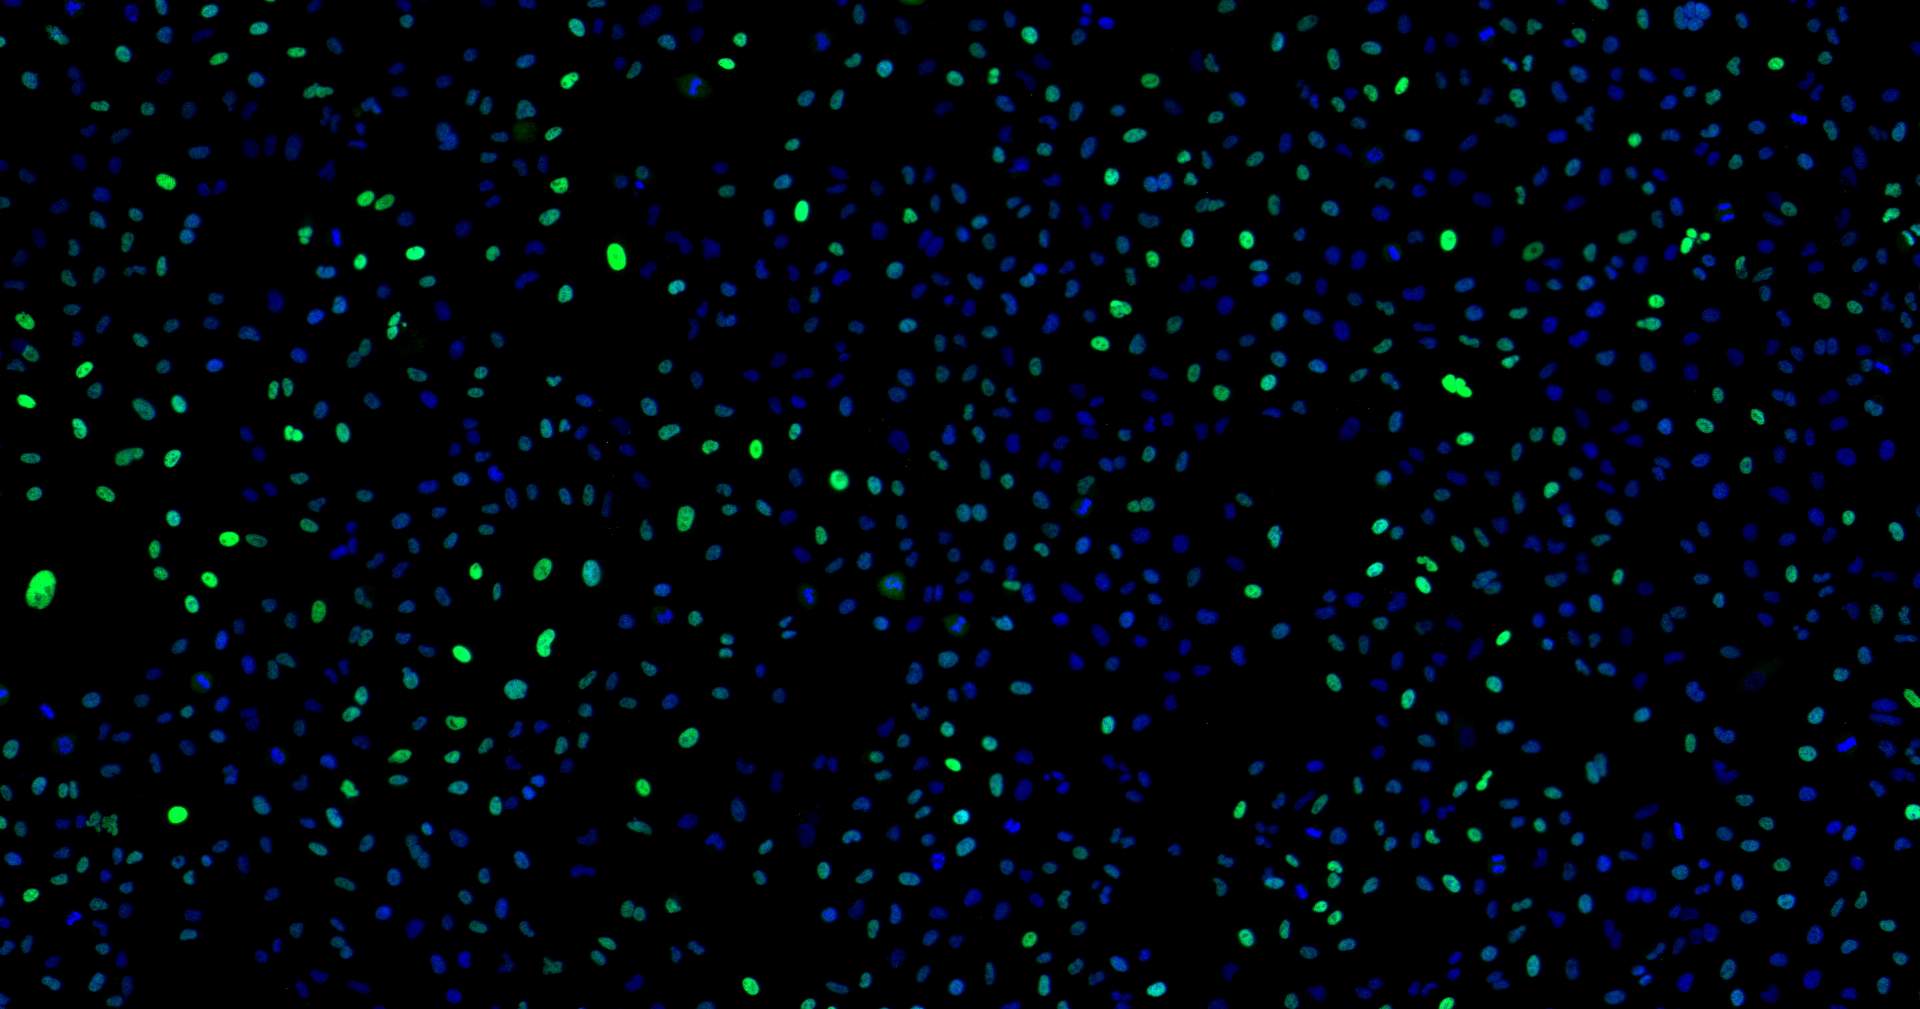

10.镜检:立即在荧光显微镜下分析样本,载玻片注意避光, DAPI能将凋亡和未凋亡的细胞核着色。

结果说明:

凋亡的细胞染色体断裂是渐进的。染色体DNA 首先在内源性的核酸水解酶的作  用下降解成较大的片段,之后部分染色体DNA 在 Ca²+和 Mg²+ 依赖的核酸内切酶作 用下,在核小体单位之间被随机切断,形成较小片段的核小体DNA 多聚体。因此在  细胞凋亡晚期 ,DNA 会被降解成更小的片段,断裂的基因组DNA 上暴露出大量的3' -OH 末端,更容易被TDT酶复合物检测。因此凋亡早期绿光信号较弱,细胞核也相对完整,凋亡信号与细胞核基本重合。细胞凋亡晚期,DNA 会被降解成较小的片段,DAPI 着色较浅或者近乎没有,此时也暴露大量3'-OH末端,结合更多的TDT绿光信号复合物,所以到晚期可能出现,只有很强的绿光信号, DAPI光很弱或者没有的结果。

正常的心、肝、肺、肾、脑等组织一般没有明显凋亡信号,如做了其他处理诱  导组织发生凋亡则会出现大量凋亡信。  (如心梗处、脑梗处凋亡信号会很明显肿瘤的坏死处表达也会很强)